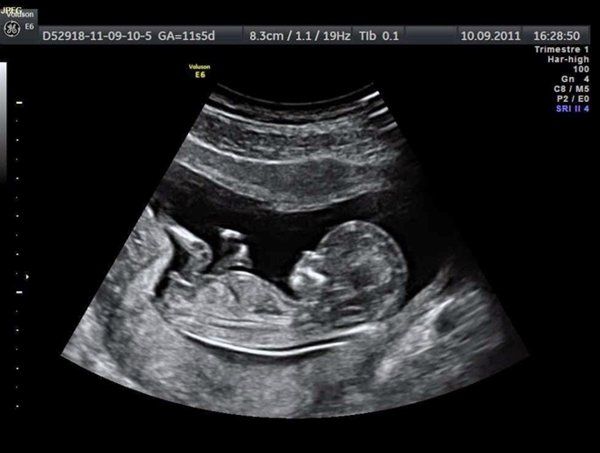

Bệnh Viện Đa Khoa tỉnh Bắc Giang cam kết cung cấp dịch vụ chăm sóc thai nhi và phụ nữ chất lượng nhất. Khoa Phụ sản được trang bị đầy đủ thiết bị hiện đại như hệ thống máy siêu âm Philips affiniti 30, hệ thống máy phẫu thuật nội soi và nhiều thiết bị khác nhập khẩu từ nước ngoài. Bệnh viện luôn đặt an toàn và hiệu quả lên hàng đầu, đặc biệt là trong công tác chăm sóc thai nhi.